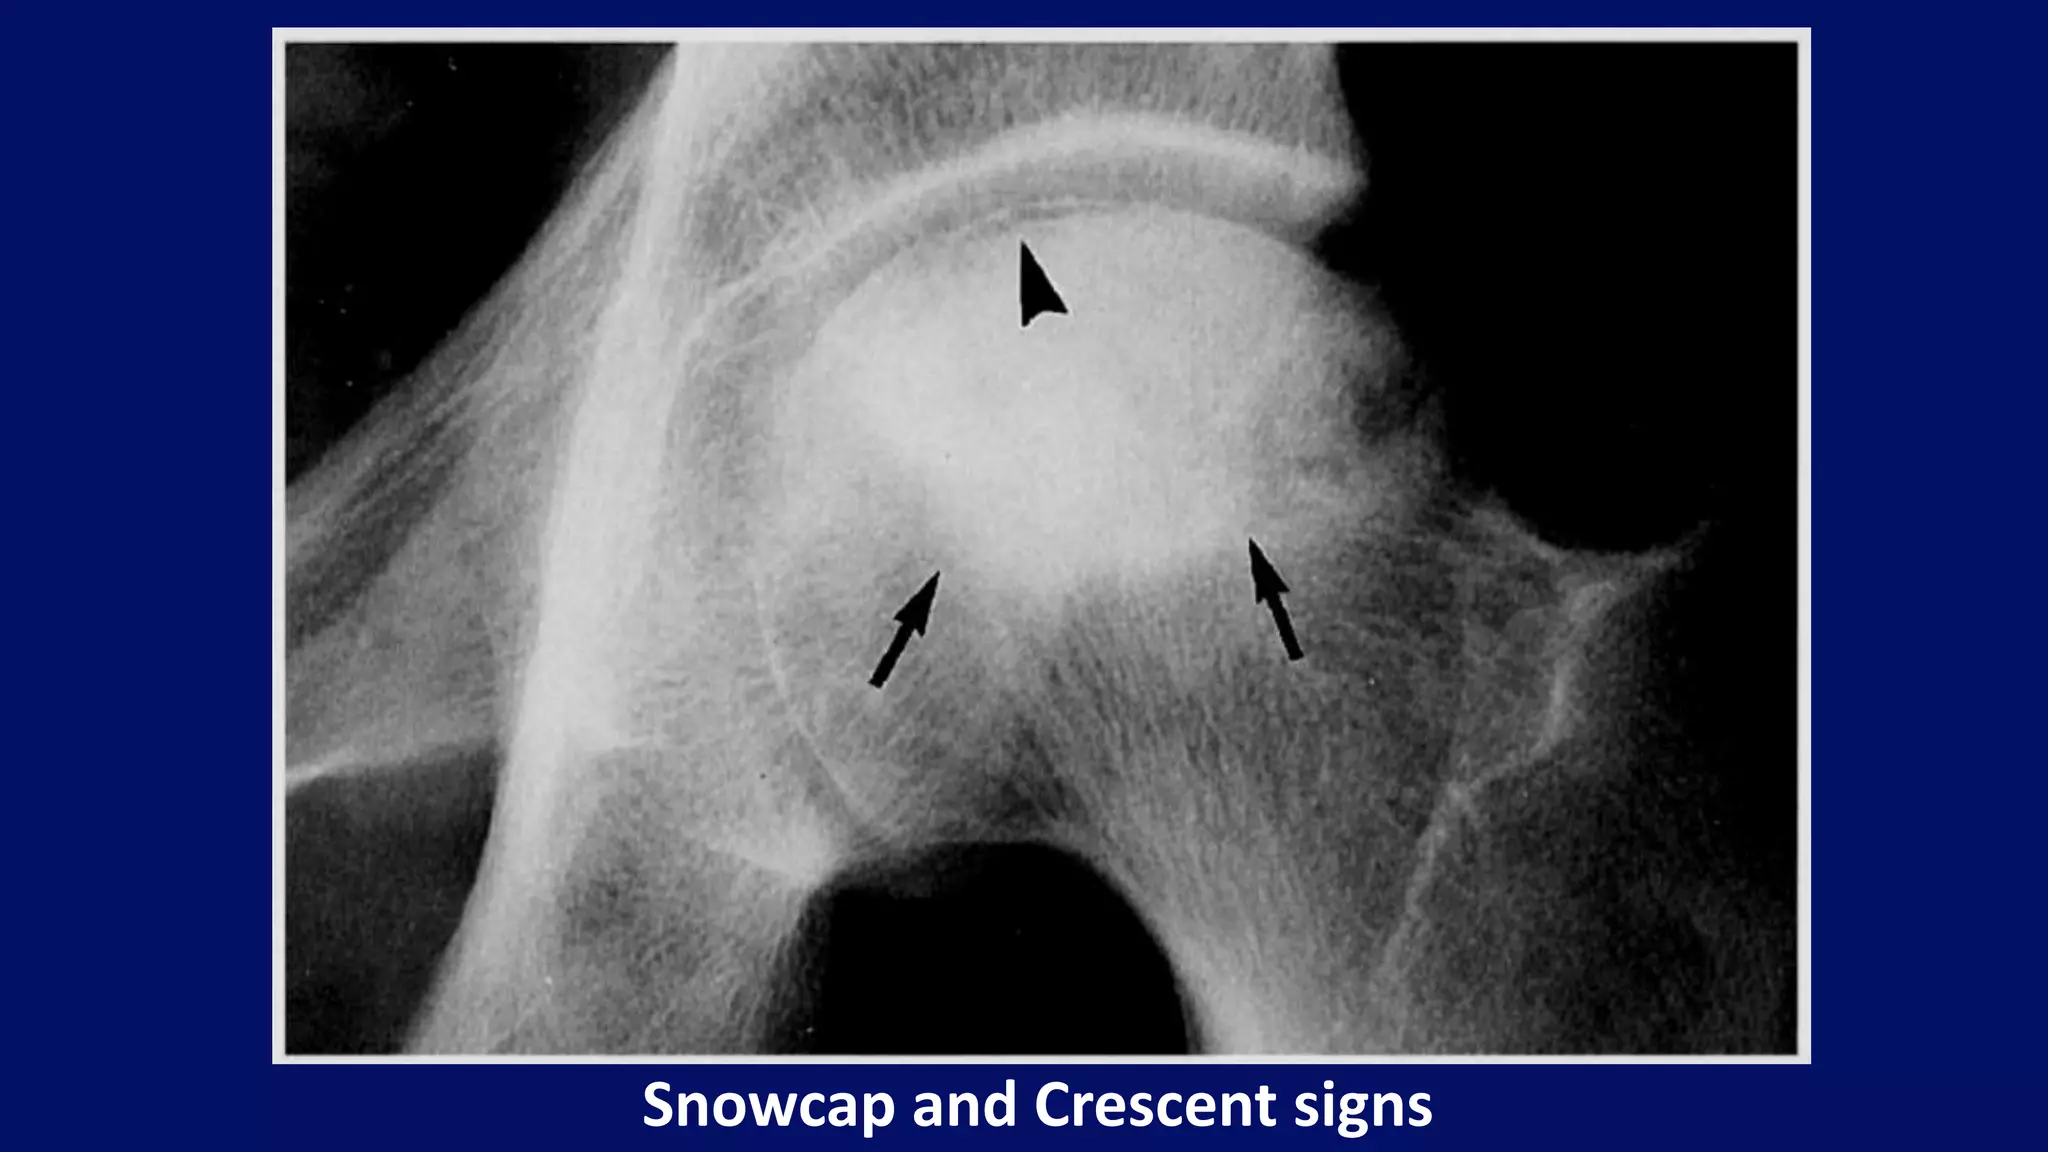

• Sclerosis (Snowcap sign)

• Crescent sign (Subchondral fracture)

Snowcap and Crescent signs

• #57 BITE AND CRESCENT SIGNS. AP Hip. Note the homogeneous increase in density (snow cap sign) involving the upper aspect of the head with a curvilinear inferior border (bite sign) (arrows). Beneath the articular cortex a subchondral fracture (crescent sign) can be seen (arrowhead).